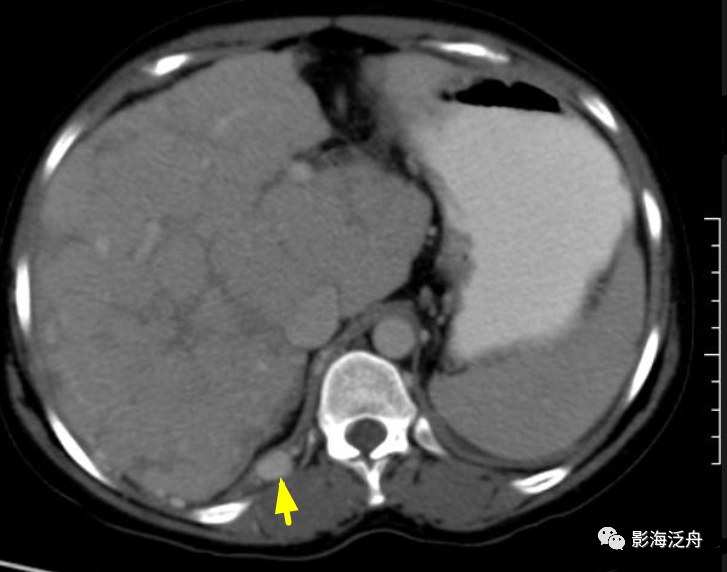

晚期布加综合征患者(下腔静脉隔膜型),肝尾状叶依然呈代偿性增大改变,局部强化相对均匀,其余肝实质强化不均,局部可见不规则裂隙样无强化区,肝包膜不光整,呈代偿性肝硬化表现。注意脊柱右旁可见侧支血管形成(黄箭),腹腔内无明显积液。